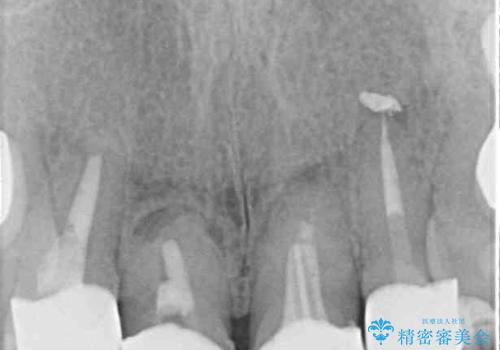

- 仮歯装着後に放置してしまい、恥ずかしいとのことで来院された患者様です。

仮歯が不適合で歯肉が腫脹していたため、しっかりと調整した新しい仮歯にして腫れを改善した上で、オールセラミッククラウンにて補綴することとしました。

日頃の歯磨きをしっかりと行ってくださるので、新しい仮歯に変えてから速やかに歯肉の状態が改善されました。

歯肉からの出血がほとんどないため精度の良い型取りができ、非常に適合の良い補綴治療を行うことができました。